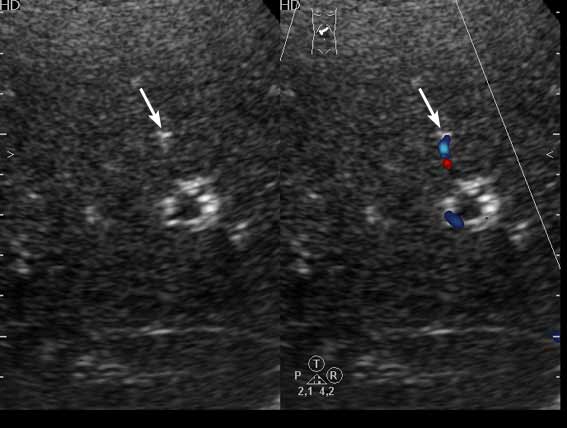

Получил данные за то, что, видимо, это мелкие конкременты в протоковой системе.

1) Эхогенные структуктуры дают твинклинг-артефакт (twinkling), характерный, например, для кальцийсодержащих образований.

2) Все пациенты, у которых наблюдалась подобная картина страдали ЖКБ, у всех был удален желчный пузырь.

Привожу еще один пример.

Женщина 70 лет,15 лет назад проведена холецистэктомия. Жалобы на боли в эпигастрии.

Видеоролик - 550 Кб